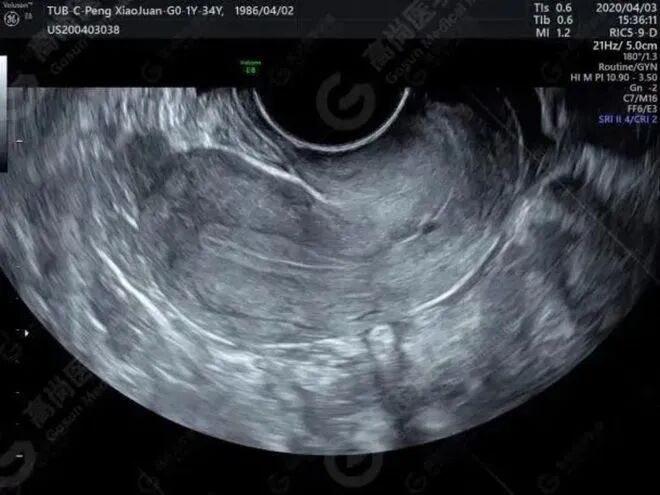

不过,如今杨华已经成年了,却还没有来月经,着实有些可疑。于是在2013年6月的一天,杨华和母亲来到了西京医院妇产科检查。没想到检查的结果出乎两人的意料,也可以说是晴天霹雳。

接诊的医生指着超声影像告诉杨华:“你患有先天性无子宫、无阴道的罕见病。”杨华看着自己的超声影像,脑海里涌现出了在课堂上学到的妇产科知识。没有子宫,意味着自己将没有器官来孕育宝宝。想到这里,杨华立刻就哭了,一旁的杨母却还不明白这个病是什么意思。

医生无奈地摇头:“你的女儿没办法怀孕。”